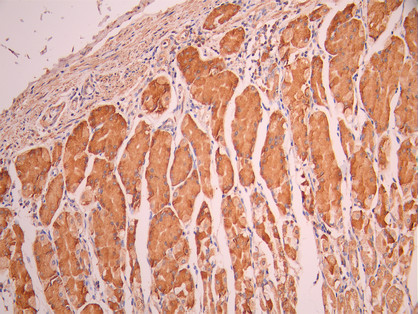

• IHC image of CSB-RA030568A0HU diluted at 1:100 and staining in paraffin-embedded human stomach tissue performed on a Leica BondTM system. After dewaxing and hydration, antigen retrieval was mediated by high pressure in a citrate buffer (pH 6.0). Section was blocked with 10% normal goat serum 30min at RT. Then primary antibody (1% BSA) was incubated at 4°C overnight. The primary is detected by a Goat anti-rabbit polymer IgG labeled by HRP and visualized using 0.05% DAB.